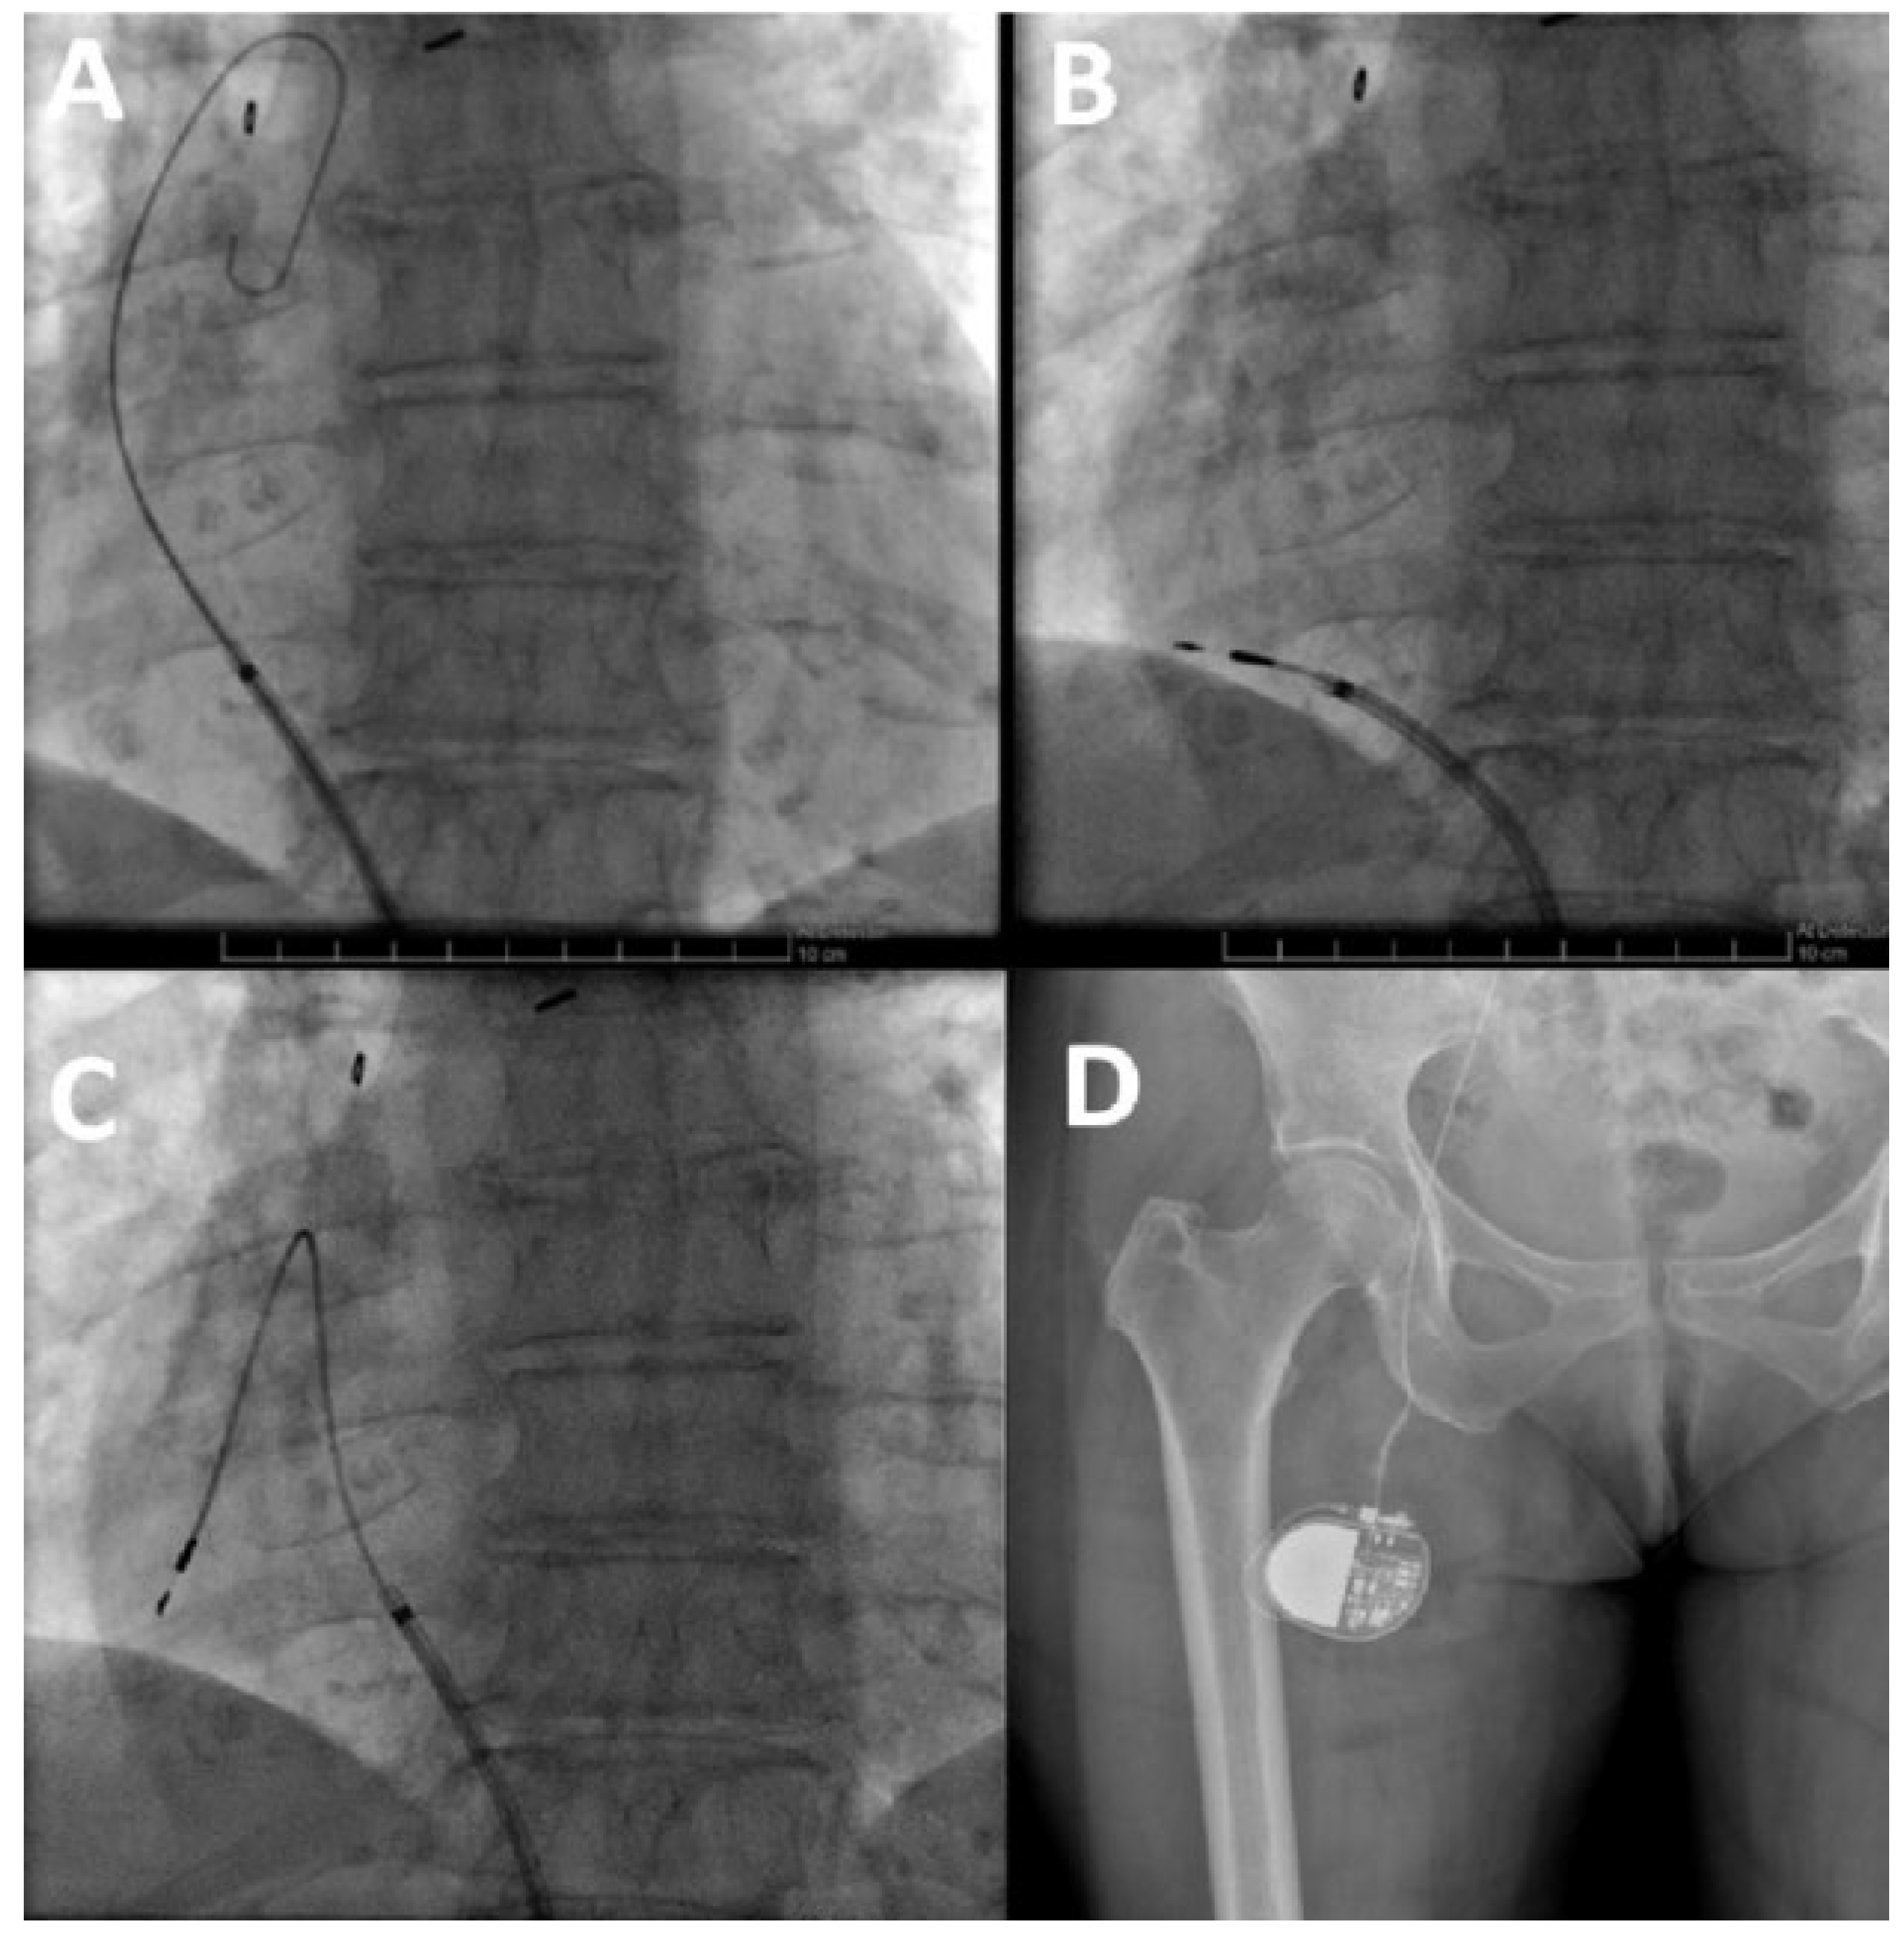

An initial approach via axillary and left subclavian venous puncture was attempted but was impossible owing to complete occlusion of this venous axis (Figure 1A). A venogram showed an occlusion of the right subclavian vein also (Figure 1B). Computed tomographic angiography indicated an obstruction of the superior vena cava and of the azygos arch with a collateral network draining through the azygos and hemiazygos network.

Figure 1. Obstruction of the left (A) and right (B) venous subclavian networks, visualised during intraoperative fluoroscopy.